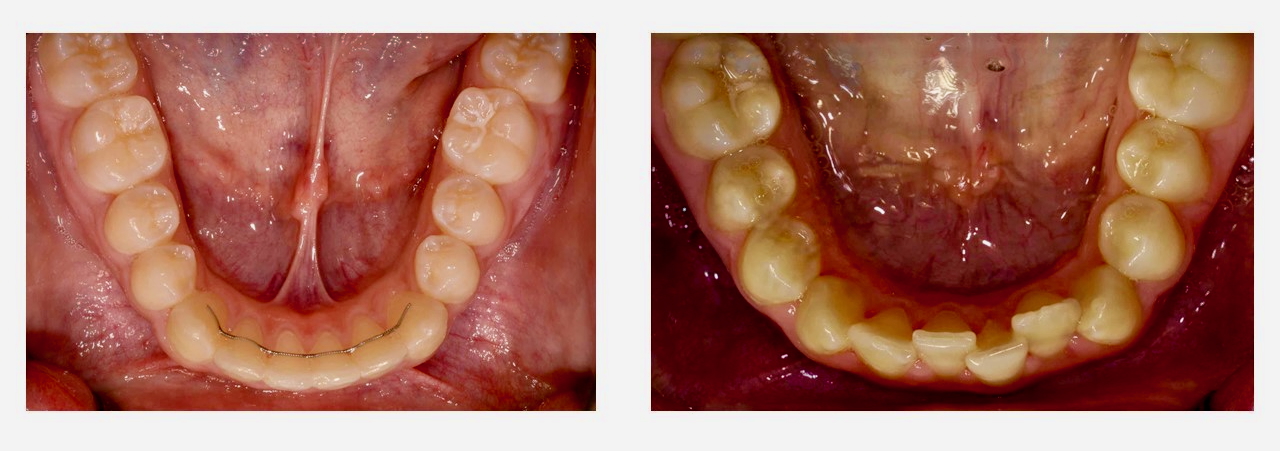

Ob man von Natur aus gerade Zähne hat oder die Zähne kieferorthopädisch begradigt wurden - unsere Zähne verschieben sich leider zeitlebens. Diese Verschiebungen erfolgen auch nach Entfernung der Weisheitszähne. Der gesamte Körper und damit auch unser Aussehen verändert sich im Laufe der Zeit. Die Zähne, die in einem relativ dünnen Knochenbett den veränderten Muskelkräften ausgesetzt sind, machen dabei keine Ausnahme. Mit festsitzenden Retainern (Bild unten links) haben wir aber die Möglichkeit die Zahnstellung langfristig zu sichern, damit Sie auch lange was von der aufwändigen Behandlung haben. Das sieht nicht nur gut aus, sondern gewährleistet auch langfristig eine gute Zahnpflege.